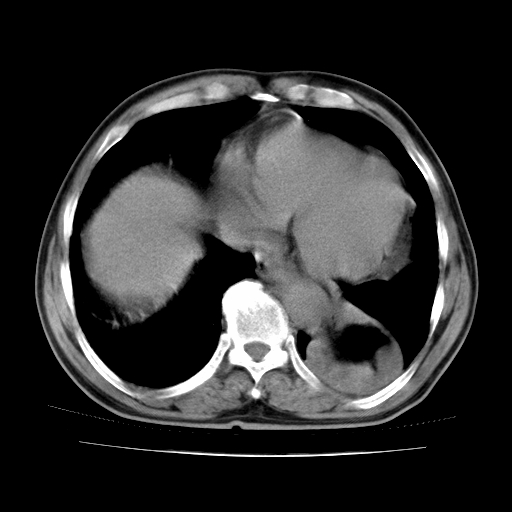

男,71岁,咳嗽,气喘10年,再发并咯血.胸片见气胸

考虑  左肺中心型肺癌伴阻塞性肺炎,肺不张,纵膈淋巴结肿大。慢支炎,肺气肿,左侧气胸肺压缩5%

左侧中央型肺癌伴纵膈淋巴结转移。

左肺中心型肺癌伴阻塞性肺炎,肺不张,纵膈淋巴结肿大

1)考虑左肺中心型肺癌伴阻塞性肺炎、左肺下叶肺不张、左侧肺气肿,纵膈淋巴结转移。2)左侧气胸(肺组织压缩约5%)。

左肺中心型肺癌伴阻塞性肺不张、肺气肿 。

1)考虑左肺中心型肺癌伴阻塞性肺炎、左肺下叶肺不张、左侧肺气肿,纵膈淋巴结转移。2)左侧气胸。